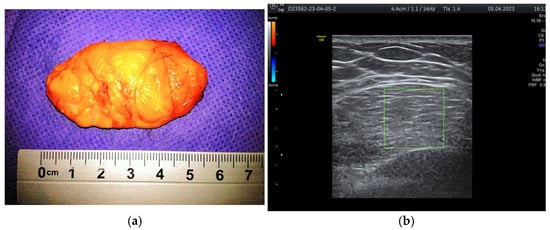

During the study period, a case initially suspected to be a hamartoma on MRI, with peripheral vessel involvement and benign axillary adenopathy, was encountered. However, an ultrasound examination established the diagnosis of a 5 × 3 cm lipoma in a 52-year-old woman, despite the tumor’s rapid growth over the course of one year (Figure 4a,b). The lipoma consisted solely of homogeneous adipose tissue, appearing hypoechoic on the ultrasound exam, with few thin striations. This case is particularly significant as it highlights the diagnostic challenges associated with differentiating between breast hamartomas and lipomas, especially in instances where rapid tumor growth is observed over one year.

Figure 4. Breast lipoma in a 52-year-old woman (a) macroscopic pathological aspect; (b) ultrasound exam—hypoechoic aspect with thin striations.